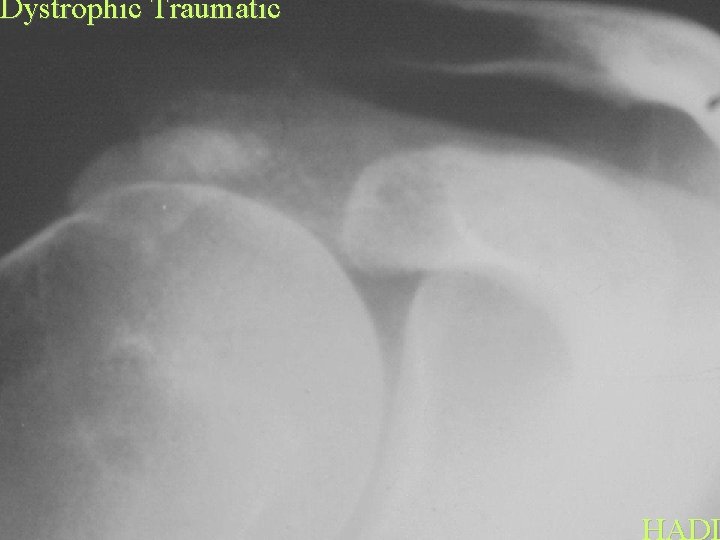

Dystrophic Traumatic HADD

Dystrophic Traumatic